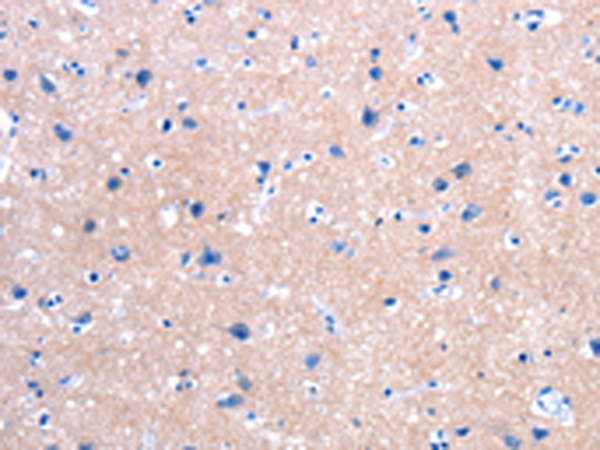

分类: 科研抗体货号: P10853别名: ALXR, HM63, FMLPX, FPR2A, FPRH1, FPRH2, FPRL1, LXA4R, FMLP-R-II应用: IHC反应种属: Human